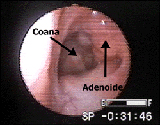

¿ES NECESARIA LA CIRUGIA DE LAS AMIGDALAS Y LAS ADENOIDES? |

Durante muchos años la amígdalo-adenoidectomía fue considerada como una panacea para las infecciones recurrentes del tracto respiratorio superior y los dolores de garganta. “Infección crónica de las amígdalas” era un diagnostico frecuente y hasta se extirpaba profilácticamente el tejido tonsilar sano.